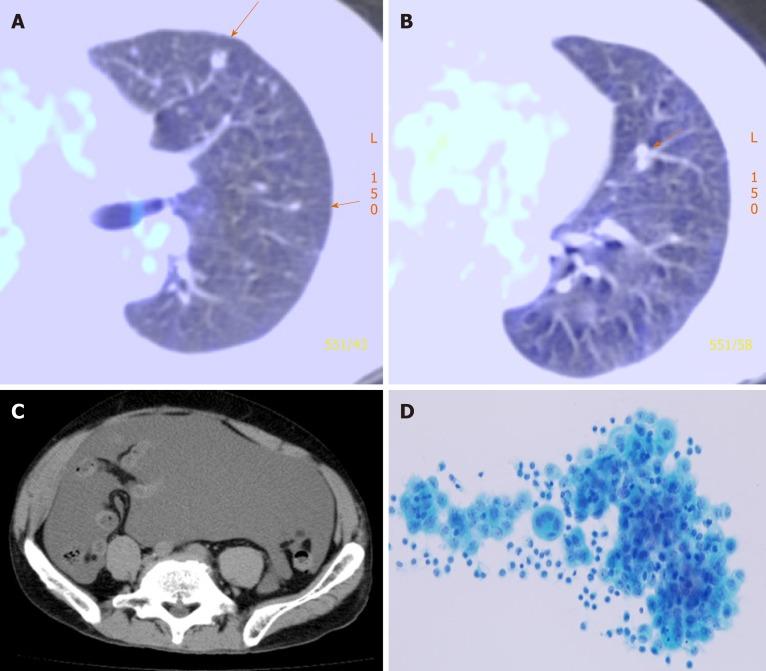

CASE SUMMARY

A 56-year-old man presented with recurrent malignant mesothelioma with massive ascites; more than 4000 mL of ascitic fluid was removed, filtered, and concentrated using KM-CART, and the cell-free ascitic fluid was reinfused into the patient to improve quality of life. Cancer cells isolated secondarily in an proliferation assay using CD-DST exhibited low sensitivity to pemetrexed and high sensitivity to gemcitabine. Treatment with gemcitabine maintained stable disease for 4 mo.

CONCLUSION

The combination of KM-CART and CD-DST may be a promising treatment option for malignant ascites associated with malignant mesothelioma.

据我们所知,我们报告了首例因复发性恶性胸膜间皮瘤导致大量腹水,采用无KM细胞和浓缩腹水回输疗法(KM-CART)进行控制的病例。KM-CART衍生的肿瘤细胞随后用于胶原凝胶微滴包埋培养药物敏感性试验(CD-DST)的细胞生长试验,以研究抗癌药物敏感性。

病例摘要

一名56岁男性,患有复发性恶性间皮瘤并伴有大量腹水;使用KM-CART去除、过滤并浓缩了超过4000 mL的腹水,将无细胞腹水回输到患者体内以改善生活质量。在使用CD-DST的增殖试验中二次分离的癌细胞对培美曲塞表现出低敏感性,对吉西他滨表现出高敏感性。吉西他滨治疗使疾病稳定了4个月。

结论